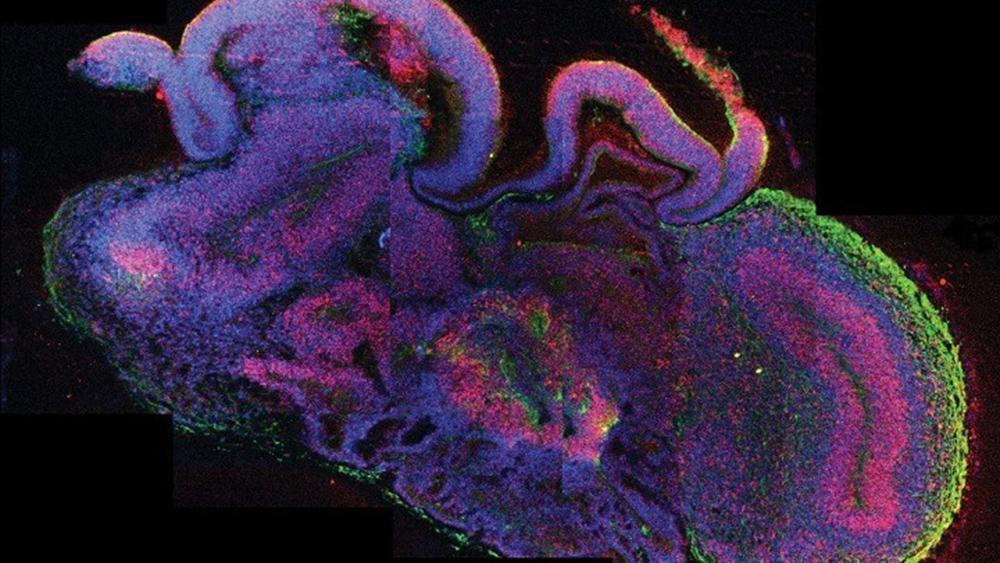

Στην πρώτη περίπτωση, οι ερευνητές από την Αυστραλία, τις ΗΠΑ, την Κίνα και τη Σιγκαπούρη, με επικεφαλής τον καθηγητή Χοσέ Πόλο του Ινστιτούτου Βιοϊατρικής Ανακάλυψης του αυστραλιανού Πανεπιστημίου Μόνας, οι οποίοι έκαναν τη σχετική δημοσίευση στο περιοδικό «Nature», αναπρογραμμάτισαν ανθρώπινα κύτταρα δέρματος (ινοβλάστες), ώστε να μετατραπούν σε μία τρισδιάστατη σφαιρική κυτταρική δομή, η οποία μοροφολογικά και μοριακά είναι παρόμοια (αν και όχι τελείως ίδια) με τη βλαστοκύστη του ανθρώπου, δηλαδή με το αρχικό -μόλις λίγων ημερών- στάδιο ανάπτυξης του εμβρύου.

Αυτό το εργαστηριακό μοντέλο εμβρύου, που ονομάστηκε iBlastoid, μπορεί πλέον να χρησιμοποιηθεί -αντί ενός κανονικού εμβρύου- για τη μελέτη της εμβρυϊκής βιολογίας. Μέχρι σήμερα ο μόνος τρόπος για να μελετηθούν οι πρώτες ημέρες του εμβρύου είναι από βλαστοκύστες που έχουν αποκτηθεί μέσω δωρεάς από τη διαδικασία της εξωσωματικής γονιμοποίησης, κάτι που περιορίζει τη διαθεσιμότητά τους. Πιο πρόσφατα, άλλοι επιστήμονες ανέπτυξαν δομές τύπου βλαστοκυστών σε ποντίκια, αλλά είναι η πρώτη φορά που κάτι ανάλογο γίνεται με τη χρήση ανθρώπινων κυττάρων.

Στη δεύτερη μελέτη, που δημοσιεύθηκε επίσης στο «Nature», οι ερευνητές, με επικεφαλής τον δρα Τζουν Γου του Νοτιοδυτικού Ιατρικού Κέντρου του Πανεπιστημίου του Τέξας, ακολούθησαν μία διαφορετική στρατηγική, ξεκινώντας από ανθρώπινα πολυδύναμα βλαστοκύτταρα, για να αναπτύξουν στο εργαστήριο τρισδιάστατα βλαστοειδή σαν τις βλαστοκύστες. Τα εργαστηριακά βλαστοειδή μοιάζουν με τις ανθρώπινες βλαστοκύστες στη μορφολογία, στο μέγεθος, στον αριθμό των κυττάρων και στη σύνθεση. Τόνισαν, πάντως, ότι αυτά τα βλαστοειδή δεν είναι ισοδύναμα ακριβώς με τις βλαστοκύστες και δεν μπορούν να εξελιχθούν σε βιώσιμο ανθρώπινο έμβρυο.